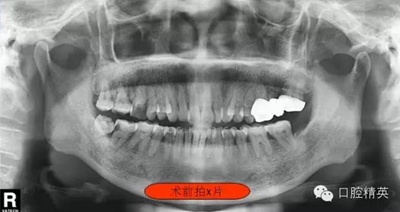

右下7根管治療(C型) 科貿(mào)嘉友收錄

這位患者女性,年齡60歲。遠(yuǎn)中鄰面深齲,探診疼痛不適。主訴有夜間疼痛加重,叩診(+),一度松動(dòng),遠(yuǎn)中根部牙槽骨吸收,診斷牙髓炎。后來右下8拔除。